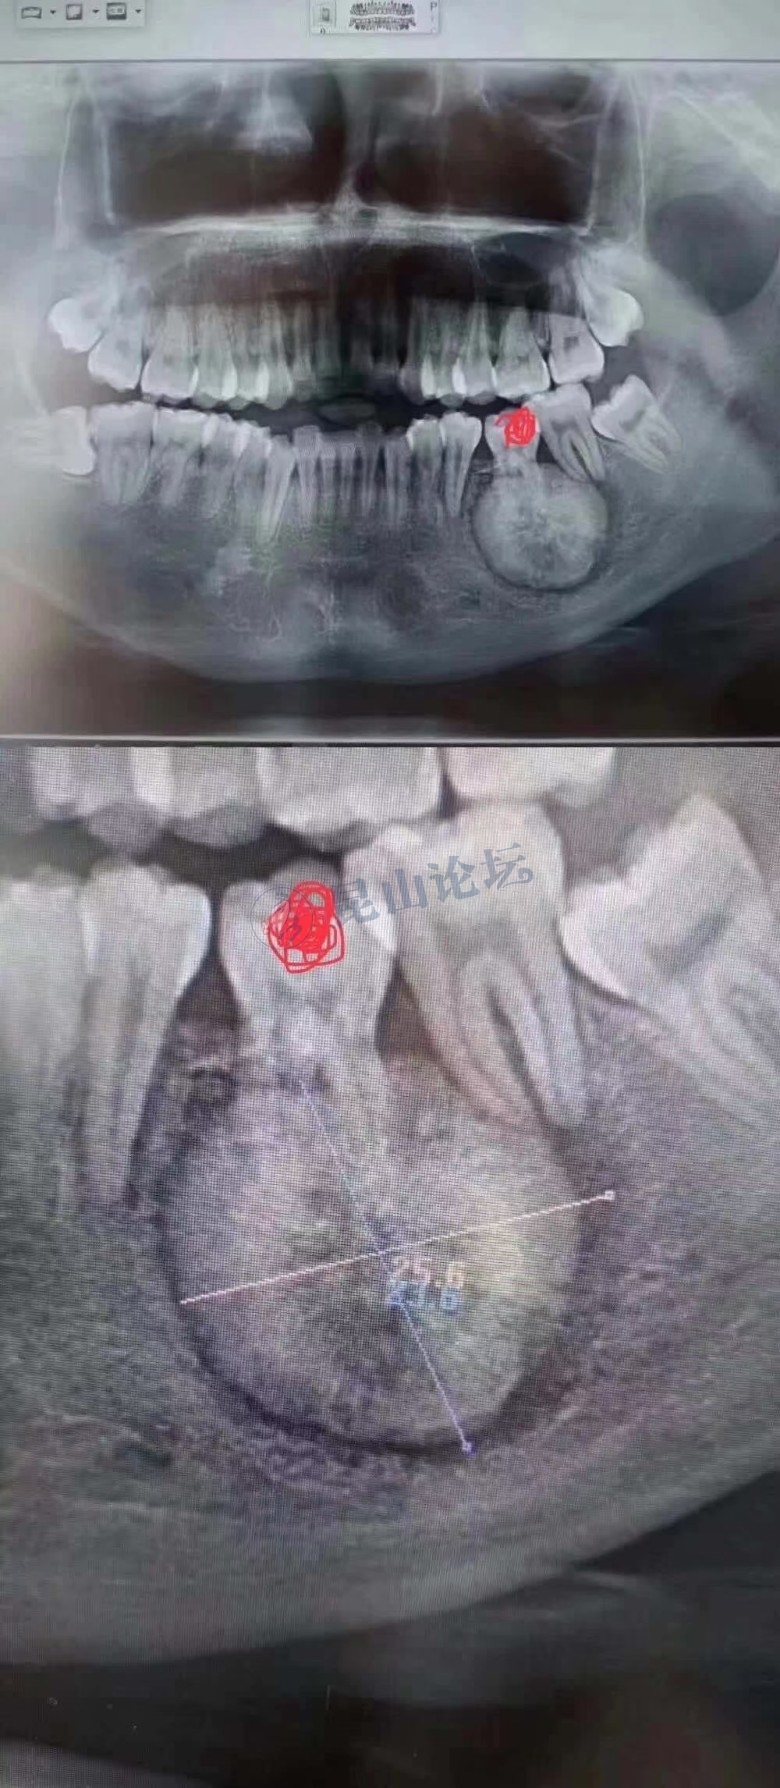

同行的一个真实案例,能给大家带来点警示患者是30多岁的年轻男子,红色标记那颗牙松动,要求拔牙,开始嫌麻烦不愿拍片,后来经过再三劝说还是拍了片。结果把所有人包括他自己都吓了一跳。估计是良性,具体还得去医院住院手术做病理检查,所以大家不要忽视一张片子带来辅助检查的重要性。